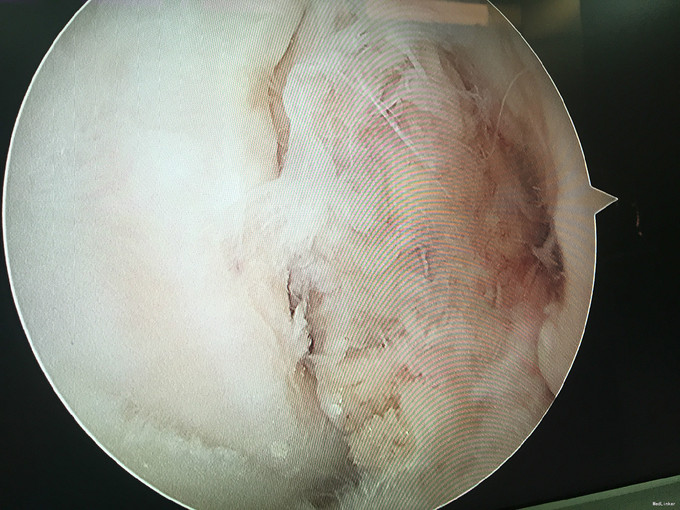

左膝扭伤后13年近1年反复不稳伴疼痛。 患者,男,39岁,13年前运动时扭伤左膝关节,当时未予重视,近1年出现左膝不稳伴疼痛,以上下楼、运动时明显,无法进行正常运动。遂于外院检查MRI(2015年3月)示:左膝关节退行性改变、左膝前交叉韧带信号异常、半月板信号异常、左膝关节内积液。为求进一步诊治来我门诊就诊,结合病史及体征,诊断“左膝半月板损伤、左膝前交叉韧带损伤”并收入院行进一步治疗。

入院诊断:左膝半月板损伤、左膝前交叉韧带损伤 治疗:入院后行左膝关节镜下外侧半月板成形+髁间窝成形+前交叉韧带自体肌腱重建手术。

随访:患者因为病程较长(十余年),术后3月膝关节才恢复正常活动度,行走正常。建议其术后1年再恢复正常运动。 讨论:该病例膝关节损伤时间较长,手术时关节已表现为提早退变(患者年龄并不大)。在前交叉韧带重建前,需要对其狭窄的髁间窝进行成形。术后恢复时间也较一般情况下延长。因此,建议关节出现病损应及时诊治。